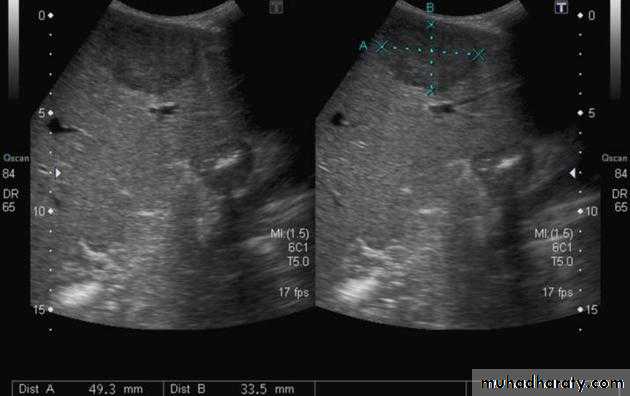

Focal masses ultrasound

Multiple masses